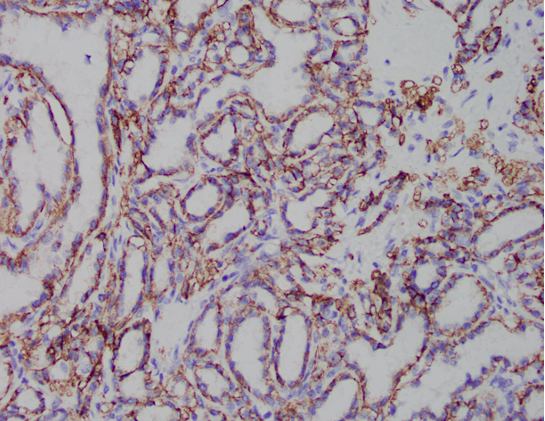

A 61-year-old female presents with a 3.5 cm renal mass. Provided are the H&E and CA9 IHC slides which show a cytoplasmic, cup-shaped distribution. CK7 shows diffuse membranous/cytoplasmic staining and AMACR and CD10 are both negative (not shown here).

Correct Answer A. This is a case of a clear cell papillary renal tumor (formerly called clear cell papillary renal cell carcinoma).

- Indolent tumor with clear glycogen-rich cytoplasm, luminal nuclear polarization, inconspicuous nucleoli, and with papillary or tubular architecture with fibrovascular stroma

- Distinctive immunohistochemical profile: positive CK7 and CAIX showing a cup-like pattern, with negative or patchy CD10 and AMACR